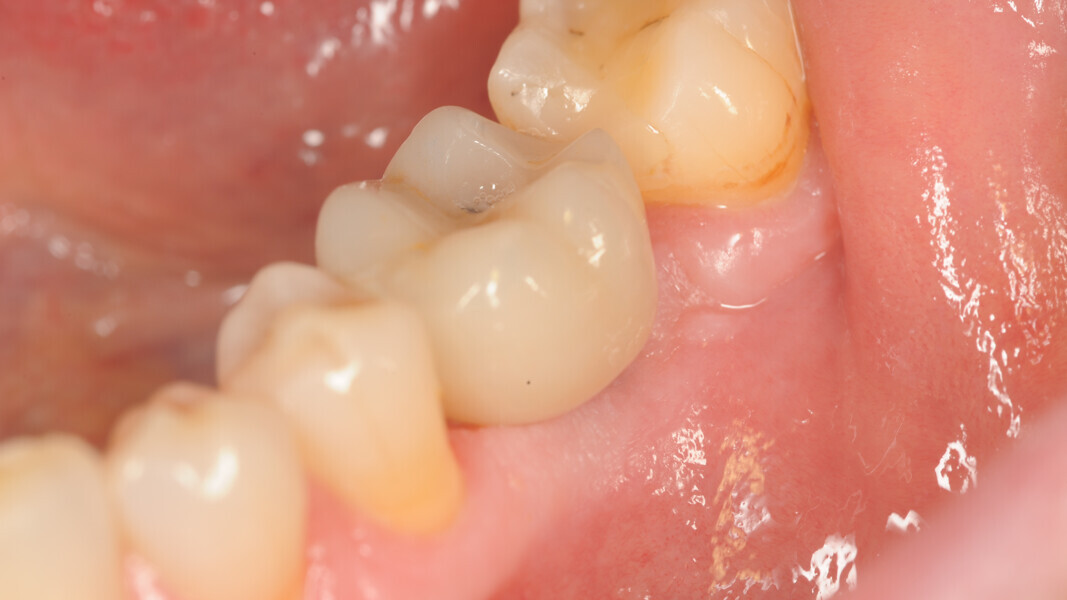

Conventional and immediate loading with final n!ce screw-retained crowns